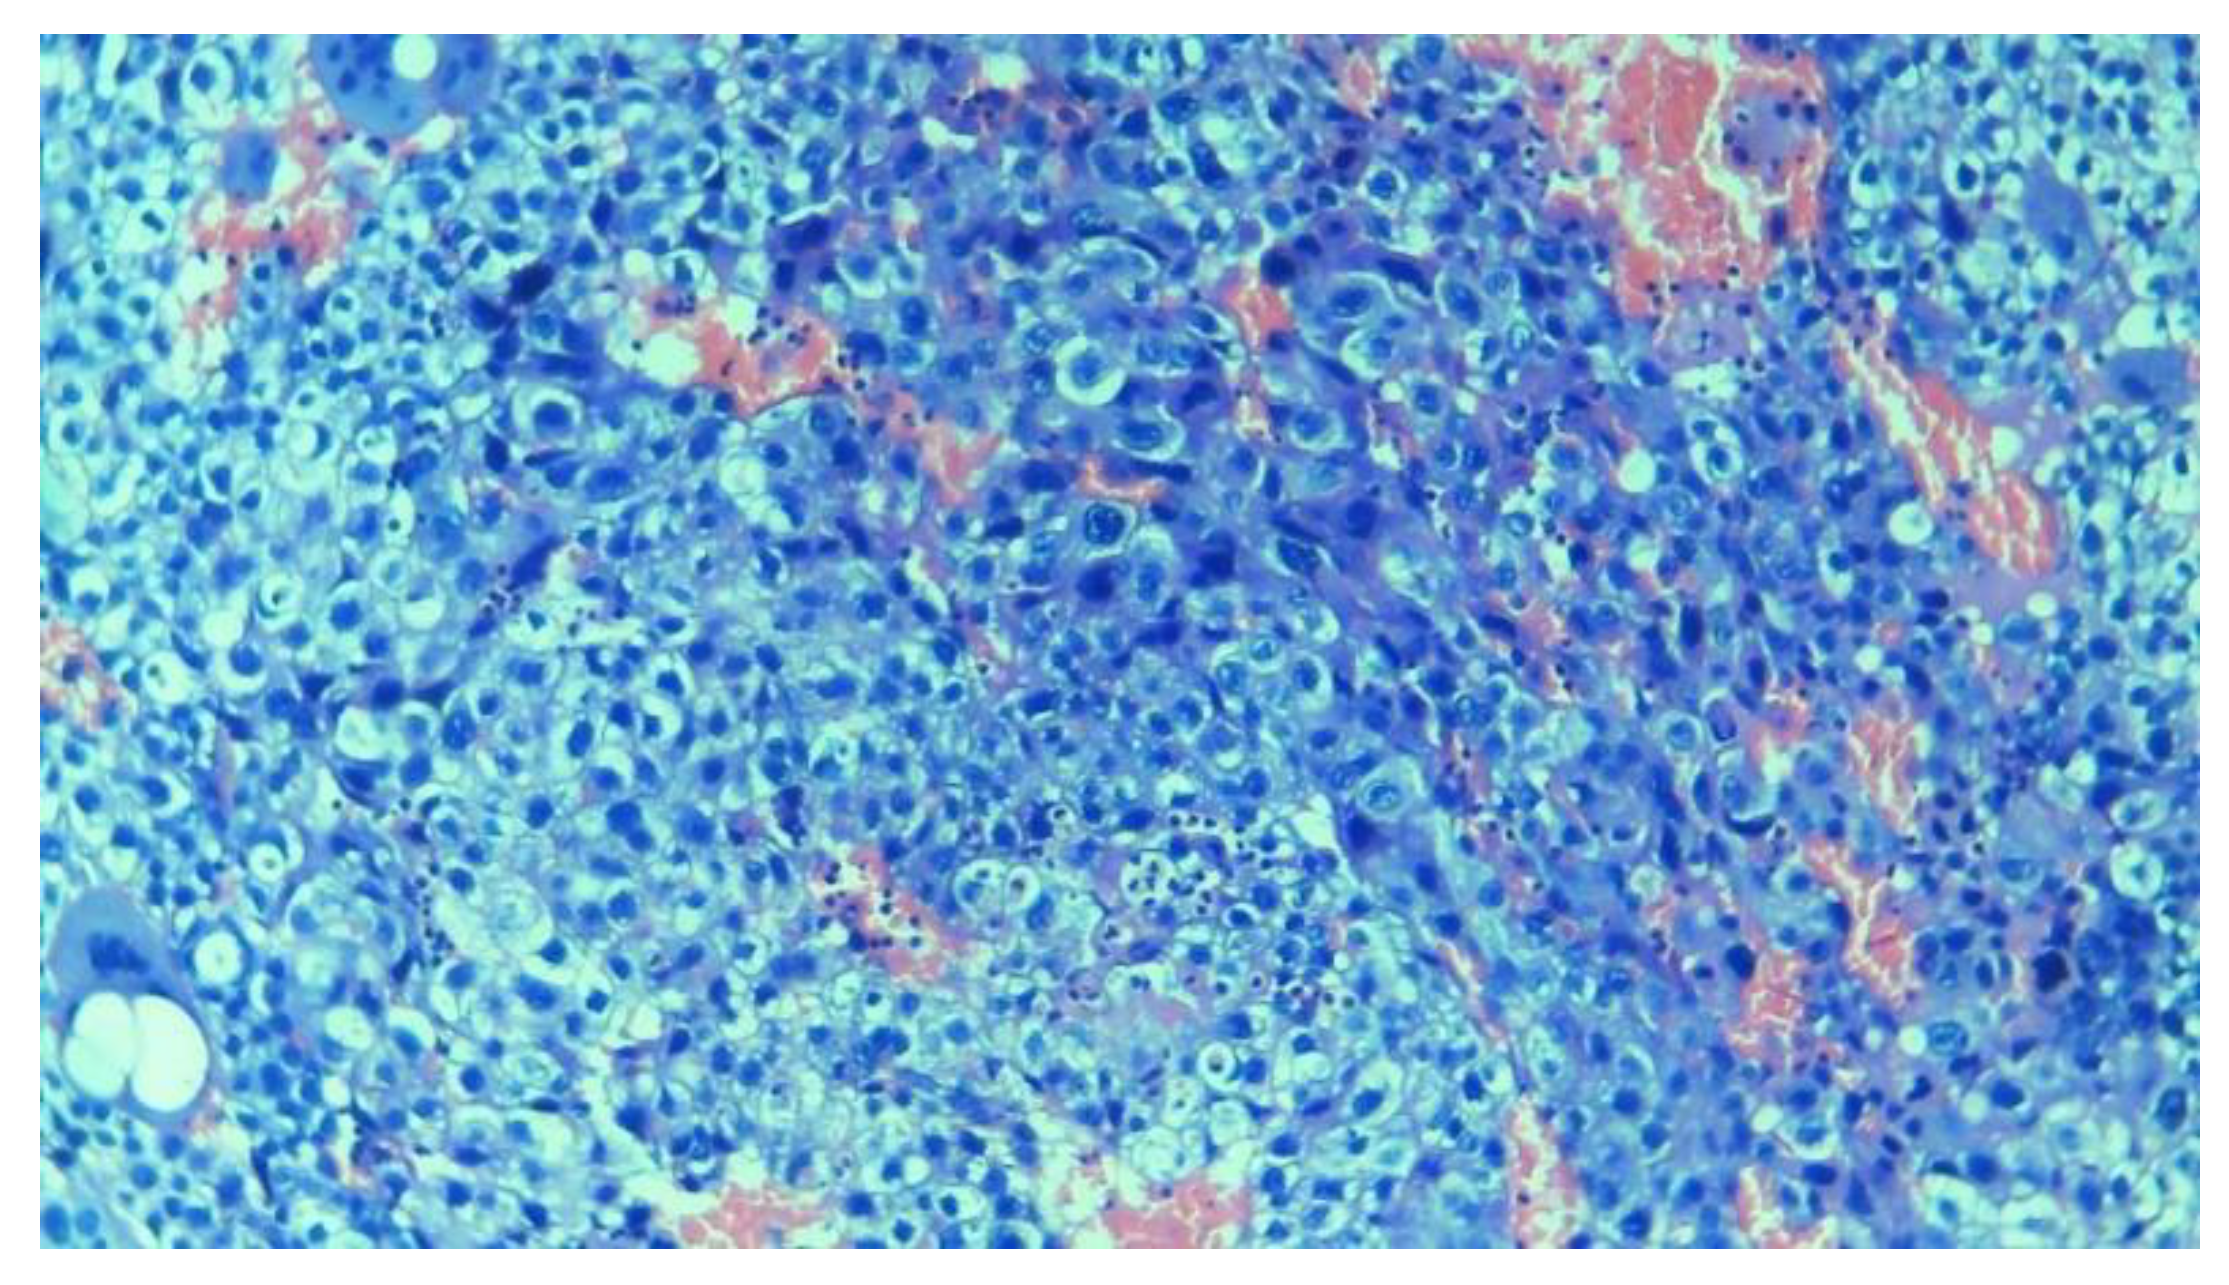

3.2.4. Trophoblastic Tissues

3.3. Baseline Models